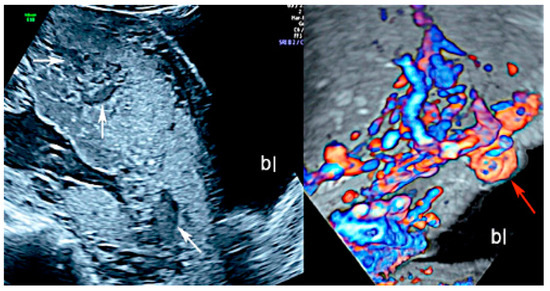

3.1.1. Placenta Accreta Spectrum

3.1.6. Chorioangioma